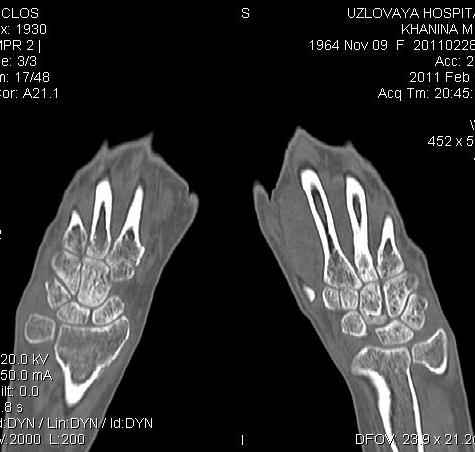

Дальнейшее лечение консервативное. Через 6 недель- гипс снят, назначено ЛФК. Пациентка крайне недовольна. Говорит, что на снимке у нее выступает кость, я ей сломал руку и.т.д. В общем началось. Пациентка прочитала в интернете наверное все, что есть по данной травме. По заключениями рентгенологов и консультанта из КДЦ областной больницы - стояние отломков допустимое. Объективно говоря- снижена высота лучевой кости, диастаз лучелоктевого сочленения, и не сросся шиловидный отросток. однако на РКТ при сравнении с другой стороной- разница незначительная.

2. сравнить снимки РКТ (с двух сторон)- так ли велико укорочение лучевой кости и лучелоктевой диастаз.